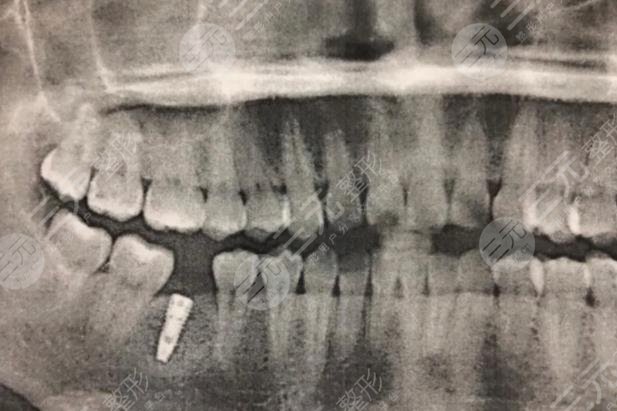

于是在朋友的陪伴下,我來(lái)到醫(yī)院,醫(yī)生親切的接待了我,醫(yī)生判斷我的牙齒已經(jīng)完全齲壞,做修復(fù)已然不可能,他建議我拿掉,然后做種植牙,種植牙降低風(fēng)險(xiǎn)系數(shù)高,使用壽命長(zhǎng),而且**較為的高。此前我比較擔(dān)心疼痛,但醫(yī)生給我解釋到種植牙所用的是局部mz,完全沒(méi)有疼痛感,其疼痛程度低于拔智齒。在比較詳細(xì)了解相關(guān)信息以后,我就決定在這家醫(yī)院做種植牙,而事實(shí)證明,我的決定是較為正確的,當(dāng)天我就做了拔牙,然后醫(yī)生給我定制了專(zhuān)門(mén)的牙冠以及種植體。

過(guò)一段時(shí)間以后就進(jìn)行種植修復(fù),誠(chéng)如醫(yī)生所言,整個(gè)過(guò)程沒(méi)有明X的痛感,回去以后有麻麻的感覺(jué)。不過(guò)好在可以忍受。做完以后,我感覺(jué)吃什么都香了,對(duì)此我較為的滿(mǎn)意,也建議大家牙齒有問(wèn)題的話(huà),應(yīng)該盡快去處理避免錯(cuò)過(guò)好的時(shí)間。